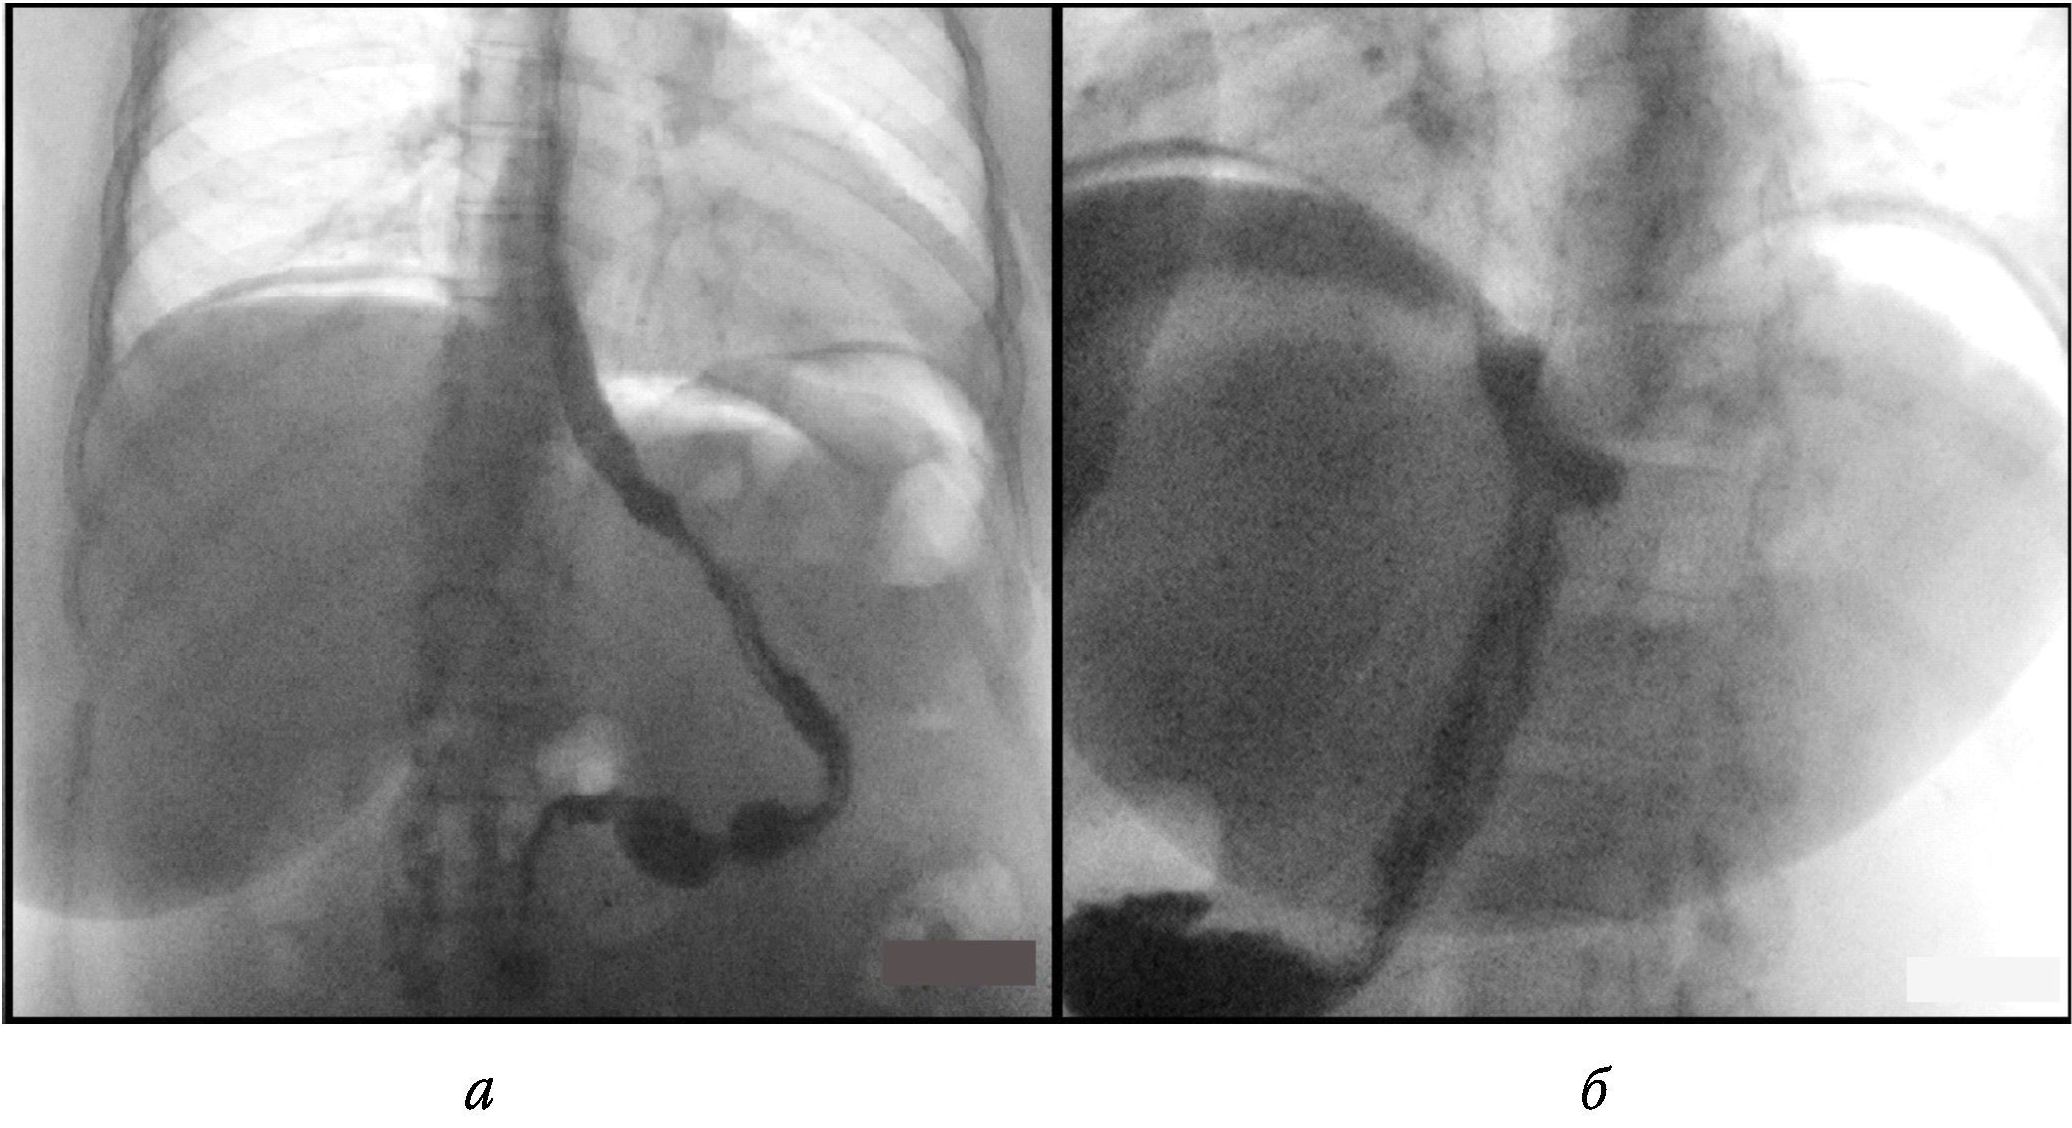

Клинический случай

Пациентка Г., 34 года, обратилась в клинику по поводу ожирения III степени по ВОЗ (рост – 173 см, вес – 120 кг, ИМТ – 40 кг/м2). Из ассоциированных с ожирением патологических состояний диагностированы гипертоническая болезнь 2-й стадии, по артериальной гипертензии II степени, риск 3, и хронический калькулезный холецистит. Из анамнеза известно, что повышенный вес с 20-летнего возраста, предпринимала попытки снижения веса с помощью различных диет, однако похудеть не удалось. После предоперационного обследования 02.05.2023 произведена лапароскопическая продольная резекция желудка с использованием калибровочного зонда 36 Fr и аппарата Echelon 60 (две зеленые, одна желтая и три синие кассеты). Укрепления степлерной линии не проводили. В течение первых суток после операции жалоб не предъявляла, общее состояние оценивалось как удовлетворительное, объем потребляемой жидкости составил 200 мл. На вторые сутки после операции стала отмечать ноющую боль в верхних отделах живота, при этом тахикардии и перитонеальных симптомов не было, температура тела оставалась нормальной. Пациентка ходила, пила воду, у нее отходили газы и был однократный стул. Выполнено УЗИ, при котором жидкостных скоплений в брюшной полости обнаружено не было. При полипозиционном рентгенологическом исследовании пищевода и желудка с водорастворимым контрастом пассаж контрастного вещества был сохранен, его затеков за пределы органов не отмечено (рис. 1).

Рис. 1. Рентгеноскопия желудка с водорастворимым контрастом в прямой (а) и боковой (б) проекциях, в положении стоя. Данных о наличии затека за пределы контуров желудка не выявлено

По данным рентгеноскопии желудка несостоятельность линии скрепочного шва выявляется только в 28–50 % случаев [2; 11]. В нашем наблюдении при полипозиционном рентгенологическом исследовании, выполненном как после первичной операции, так и после релапароскопии, не было зафиксировано подтекания контрастного вещества за пределы желудка. Аналогичные данные по низкой эффективности рентгеноскопии желудка отражены в работах А.Г. Хитарьян и соавт. [12], Л.П. Котельниковой и соавт. [13]. Поэтому на сегодняшний день КТ с пероральным и/или внутривенным введением контраста следует рассматривать как наиболее ценный неинвазивный метод диагностики несостоятельности линии степлерного шва, что подтверждает описанный нами случай и данные литературы, свидетельствующие о 86–90%-ной информативности [14].